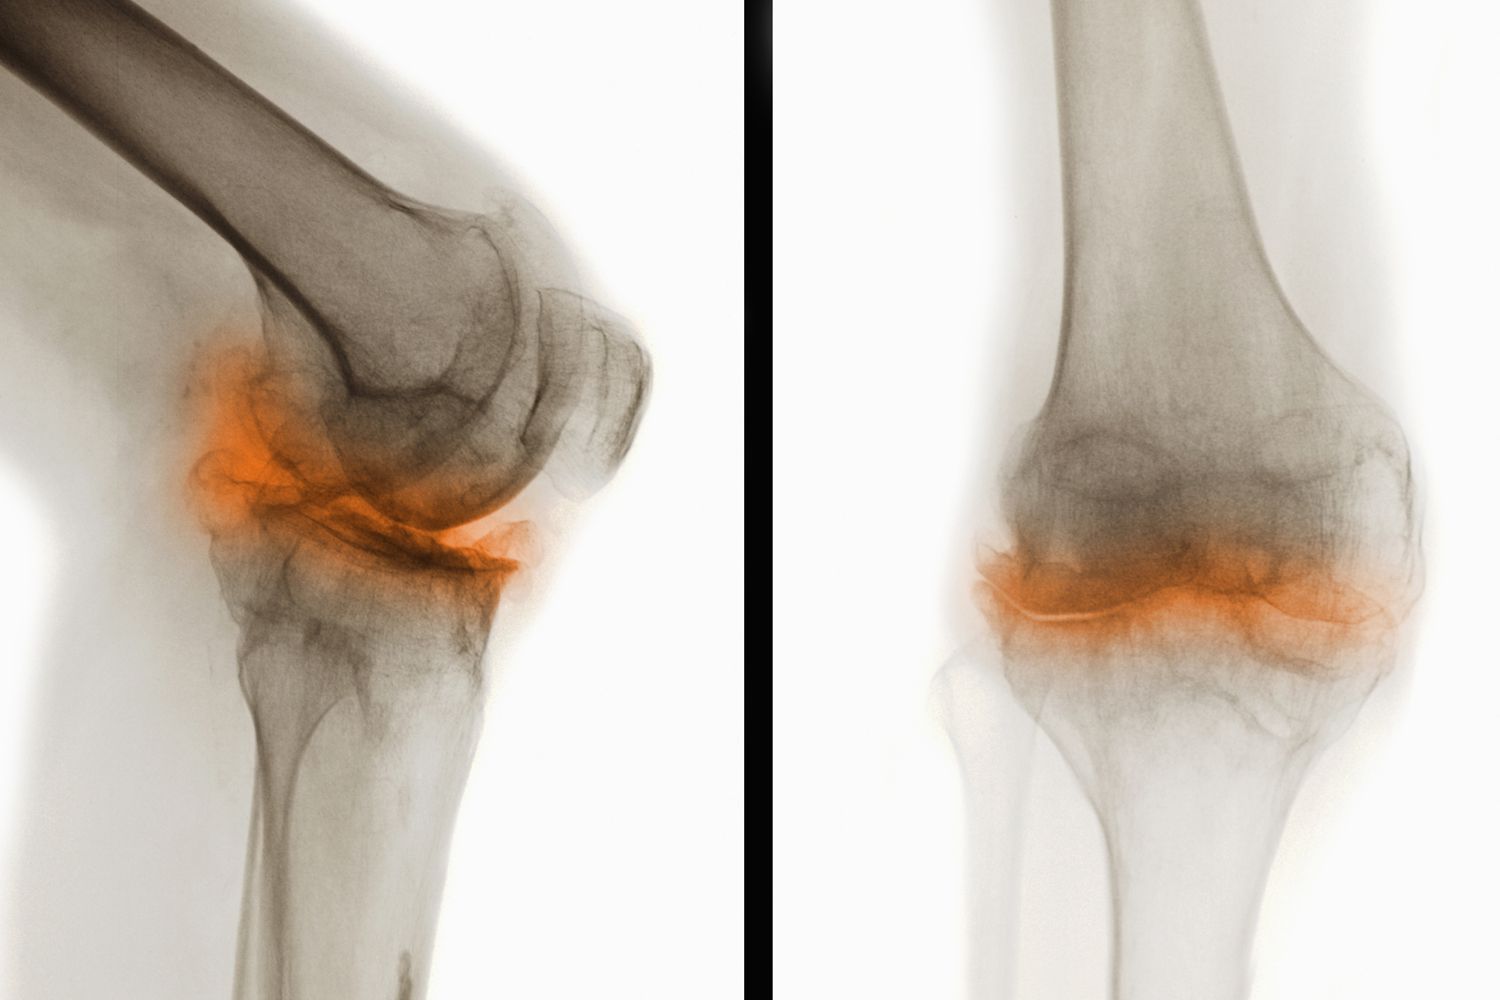

骨關(guān)節(jié)炎(Osteoarthritis,簡稱OA)是一種常見的慢性退行性關(guān)節(jié)疾病,主要表現(xiàn)為關(guān)節(jié)軟骨的退化和破壞,導(dǎo)致關(guān)節(jié)疼痛、僵硬和功能障礙。這種疾病通常發(fā)生在中老年人群中,尤其是負重較大的膝關(guān)節(jié)、髖關(guān)節(jié)、脊柱及遠側(cè)指間關(guān)節(jié)等部位。